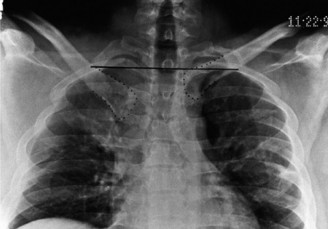

CASE 20 A 72-year-old, right-hand-dominant male with a history of type 2 diabetes, hypertension, and coronary artery disease presents to clinic for a second opinion regarding worsening left shoulder pain 8 months after undergoing a left total shoulder arthroplasty. He had an uncomplicated procedure and has had no major postoperative complications thus far; however, he has never been completely pain free since his procedure. He denies any recent trauma, fevers, chills, or drainage from the incision site. On examination, the incision sites are clean, dry, and intact, and he has mild tenderness to palpation diffusely over the left shoulder as well as decreased range of motion. Imaging is shown in Figure 2–55.

Figure 2–55

The correct answer is (C). This patient’s story of acutely worsening pain without known trauma and with a history of orthopaedic implants is suspicious for infection. Risk factors for infection include rheumatoid arthritis, diabetes mellitus, systemic lupus erythematosus, malignancy, immunosuppression, etc. The first step in this diagnosis would be CT arthrogram of the shoulder to evaluate for loosening as sign of infection. A is incorrect as, although infection is on the differential, it has not yet definitively been diagnosed and therefore an immediate irrigation and debridement would not be indicated. MRI (Choice B) might be helpful in identifying a joint effusion or bony edema/signal intensity but would not provide as useful information as synovial fluid would at this point. Choice D is incorrect because the patient must be worked up for infection before deciding on conservative

CT arthrograms of the patient’s left shoulder are shown in Figure 2–56. CRP is <3, ESR 45. The patient continues to have pain, so you decide to perform arthroscopic biopsy to obtain tissue cultures. Frozen sections show <5 PMNs per hpf, and Gram stains are all negative.

Figure 2–56

The correct answer is (B). Figure shows contrast under the glenoid component. Given the patient’s normal inflammatory markers and frozen sections combined with continued pain and loosening on CT, infection with P. acnes(an organism that is very difficult to isolate) should be investigated by holding any cultures for at least 2 weeks to see if it will eventually grow. Chocolate agar (Choice C) is mainly used for growing species such as H. influenzae and Neisseria meningitidis not P. acnes. A is incorrect since the patient’s cell count and frozen sections are clearly abnormal, therefore referral to pain clinic would not be appropriate. However, Choice D would be too aggressive an approach given that no organisms have been isolated, frozen sections show <5 PMNs per hpf, and the patient has relatively normal inflammatory markers.